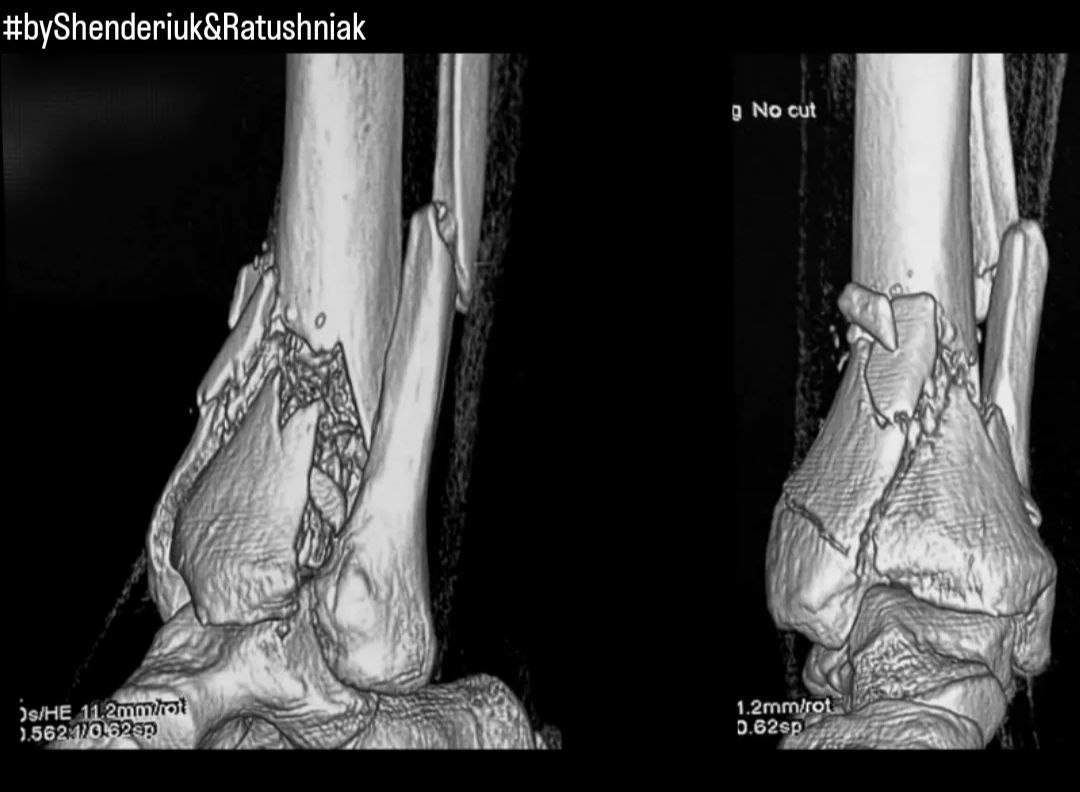

Лікування переломів гомілково-ступеневого суглоба

Загальні відомості Переломи гомілково-ступеневого суглоба є одними з найпоширеніших серед усіх інших. Вони супроводжуються різким зменшенням якості життя внаслідок втратою опороздатності